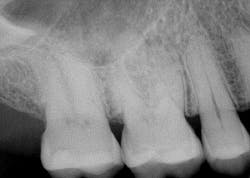

- Radiographic examination—It is rare to see a crack on a radiograph, but bone resorption and periodontal/pulpal health can be observed.

A radiograph assessment revealed a slight radiolucency at the apex of the palatal root on tooth No. 3 (figure 8). Biting and percussion was WNL; probing depths were 6 mm interproximal and 3–4 mm on the facial/lingual. Cold and electric pulp tests were negative. The vestibular area in the No. 3–4 area was tender to palpation. Clinically, a large fracture line was noted on the lingual and on the distal marginal ridge (figure 9).

Diagnosis: Necrotic No. 3 with likely association of extended fracture line into the pulpal space. Recommendations were given to the patient, who opted for extraction and eventual implant placement. Upon removal of the tooth, the following was noted (figure 10):